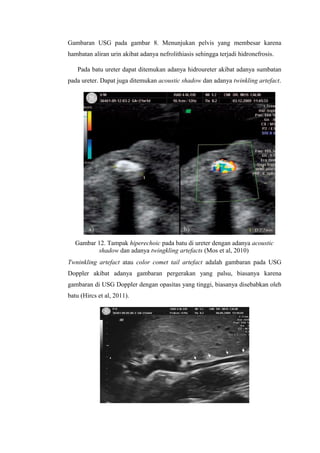

Gambar 3. Foto polos abdomen normal

Pada pasien penderita batu ginjal yang dilakukan pemeriksaan foto polos abdomen

dapat terlihat bentuk dari pelvis renalis yang melebar dengan gambaran radioopak.

Gambar 4. Terlihat gambaran radioopak membentuk pelvis renalis yang

membesar. Menandakan batu pada kalix minor dan kalix mayor. Pada gambaran

radiologis disebut dengan Batu Staghorn